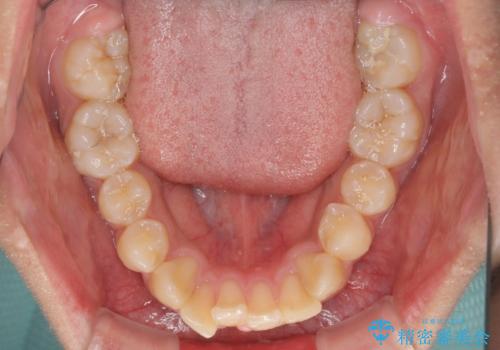

膨らんだ口元 ワイヤー装置での抜歯矯正

上下前歯が著しく前突している状態であったので、上下左右の第1小臼歯4本を抜歯し、ワイヤー装置にて矯正治療を行うこととしました。

舌の突出癖により、前突になったと考えられたため、舌のトレーニングをしっかりと行うよう指導しました。